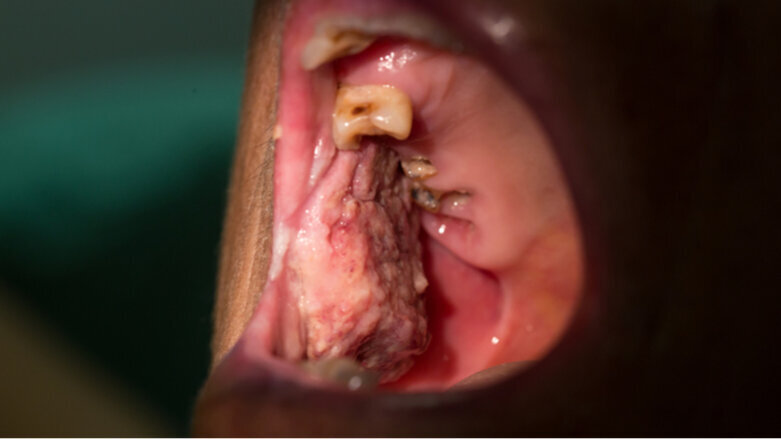

DUBLIN, Ireland: According to the Irish Cancer Society, about 550 people are affected by mouth, head and neck cancers in Ireland each year. As patients are less likely to visit their dental practice owing to SARS-CoV-2 and the associated risk of infection, dentists have warned that a high number of oral cancers could be missed or diagnosed at a very late stage.

During the lockdown, Stassen identified two cases of oral cancer using photographs his patients had sent him. However, many patients do not recognise or do not act on symptoms for oral cancer because they are either concerned about possible infection with SARS-CoV-2 or unaware that emergency dental services have continued to operate during the lockdown. Before the pandemic, dentists helped to discover between 150 and 180 cases of mouth, head and neck cancers each year, noted Stassen.

Cases of oral cancer caught at an early stage have a survival rate of approximately 90% and may only require surgery. However, cases caught at a later stage of development have a decreased survival rate of only 5%–10%. Check-ups are important not only for those patients who have developed symptoms during the pandemic but also for those who have recovered from the disease. This is in order to make sure that the cancer has not returned.